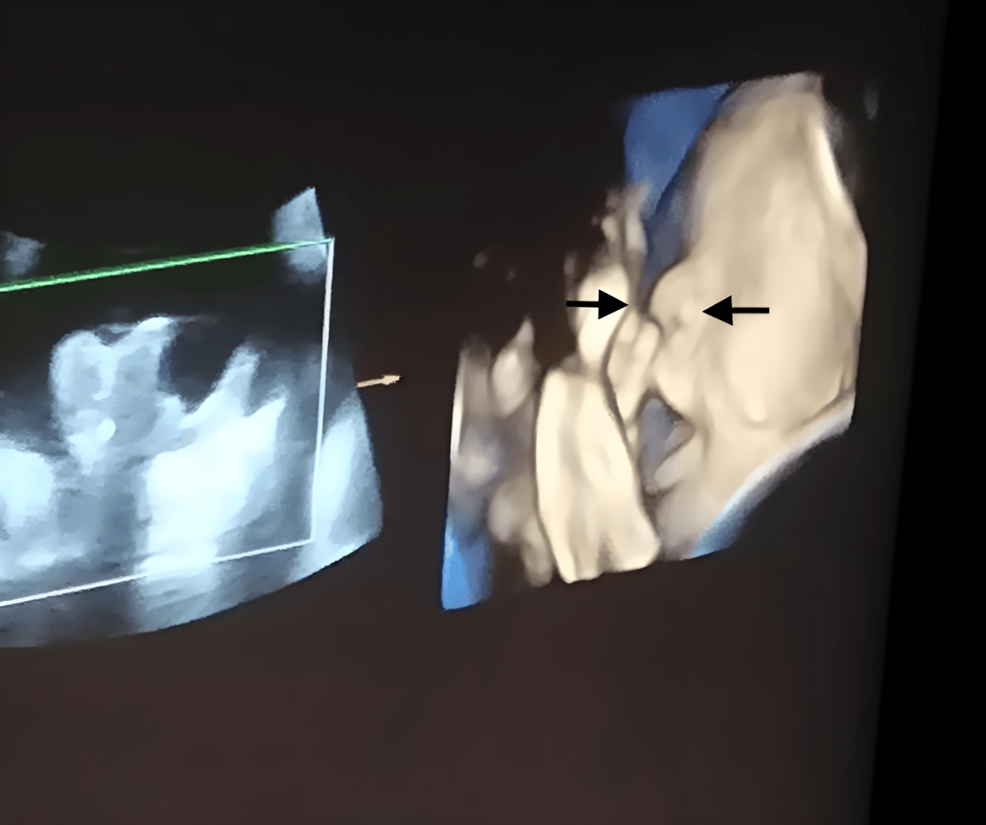

• Imaging confirmation: high‑resolution ultrasound + Doppler studies to map fetal positions, chorionicity, and vascular connections.

2. Use 3‑D ultrasound for precise fetal mapping; it decreases needle passes by ~30 %.